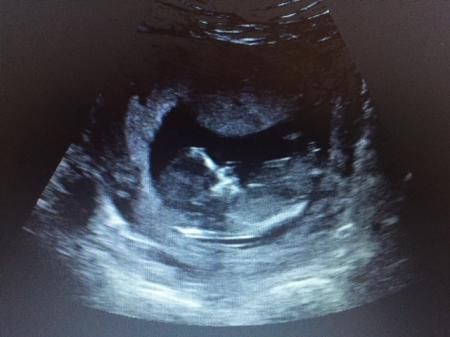

Hallihallo! Heute habe ich durch Zufall von der nub Methode erfahren, total spannend wie ich finde: NUB Theorie :) da geht es darum, wenn die geschlechtsorgane gebildet werden steht eine Arzt schwanz, und je nachdem wie das absteht (parallel zur Wirbelsäule = Mädchen, nach oben = Junge) "bestimmt" man das Geschlecht. Hier noch genauer: http://www.ingender.com/gender-ultrasound/nub-theory.aspx Kennt das jemand von euch? Vielleicht wollen wir ja gemeinsam raten um uns die Wartezeit zu verkürzen ;) schicke ich mal anbei mein Bild von der nfm in der 13. ssw - was meint ihr? Freu mich auf Austausch :)

ups, hier das bild, hat sich nicht geladen ;)

Bild zu